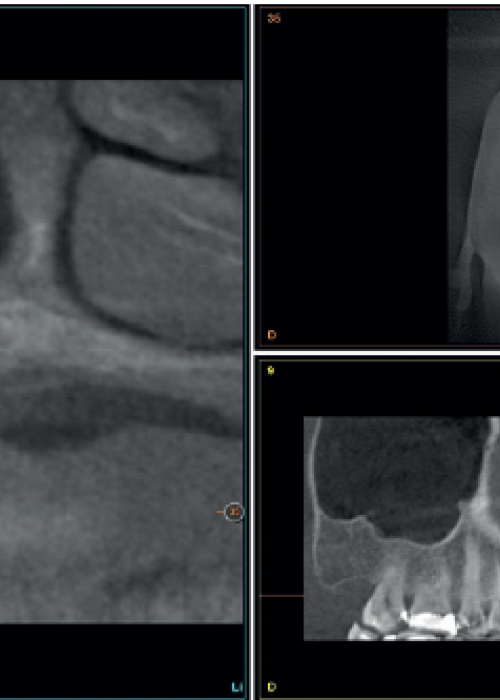

Implant explantation poorly positioned in an aesthetic sector and subsequent regeneration with block grafting. Clinical case

Explantación de implante mal posicionado en sector estético y regeneración posterior con injerto en bloque